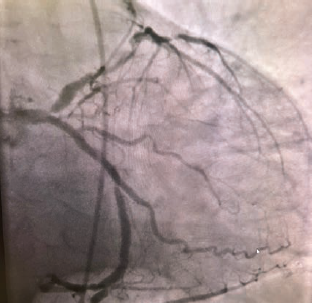

Coronary anatomy revealed a normal left main and an occlusion in the ostial left anterior descending (LAD) at 95%, proximal LAD 70%, mid-LAD 90%, mid left circumflex (LCx) 85%, obtuse marginal (OM)1 70%, OM2 40%, 1st left posterolateral artery 70%, ostial left posterior descending artery 90%, and a right coronary artery (RCA) 100% chronic total occlusion (CTO) (Figures 2-4).